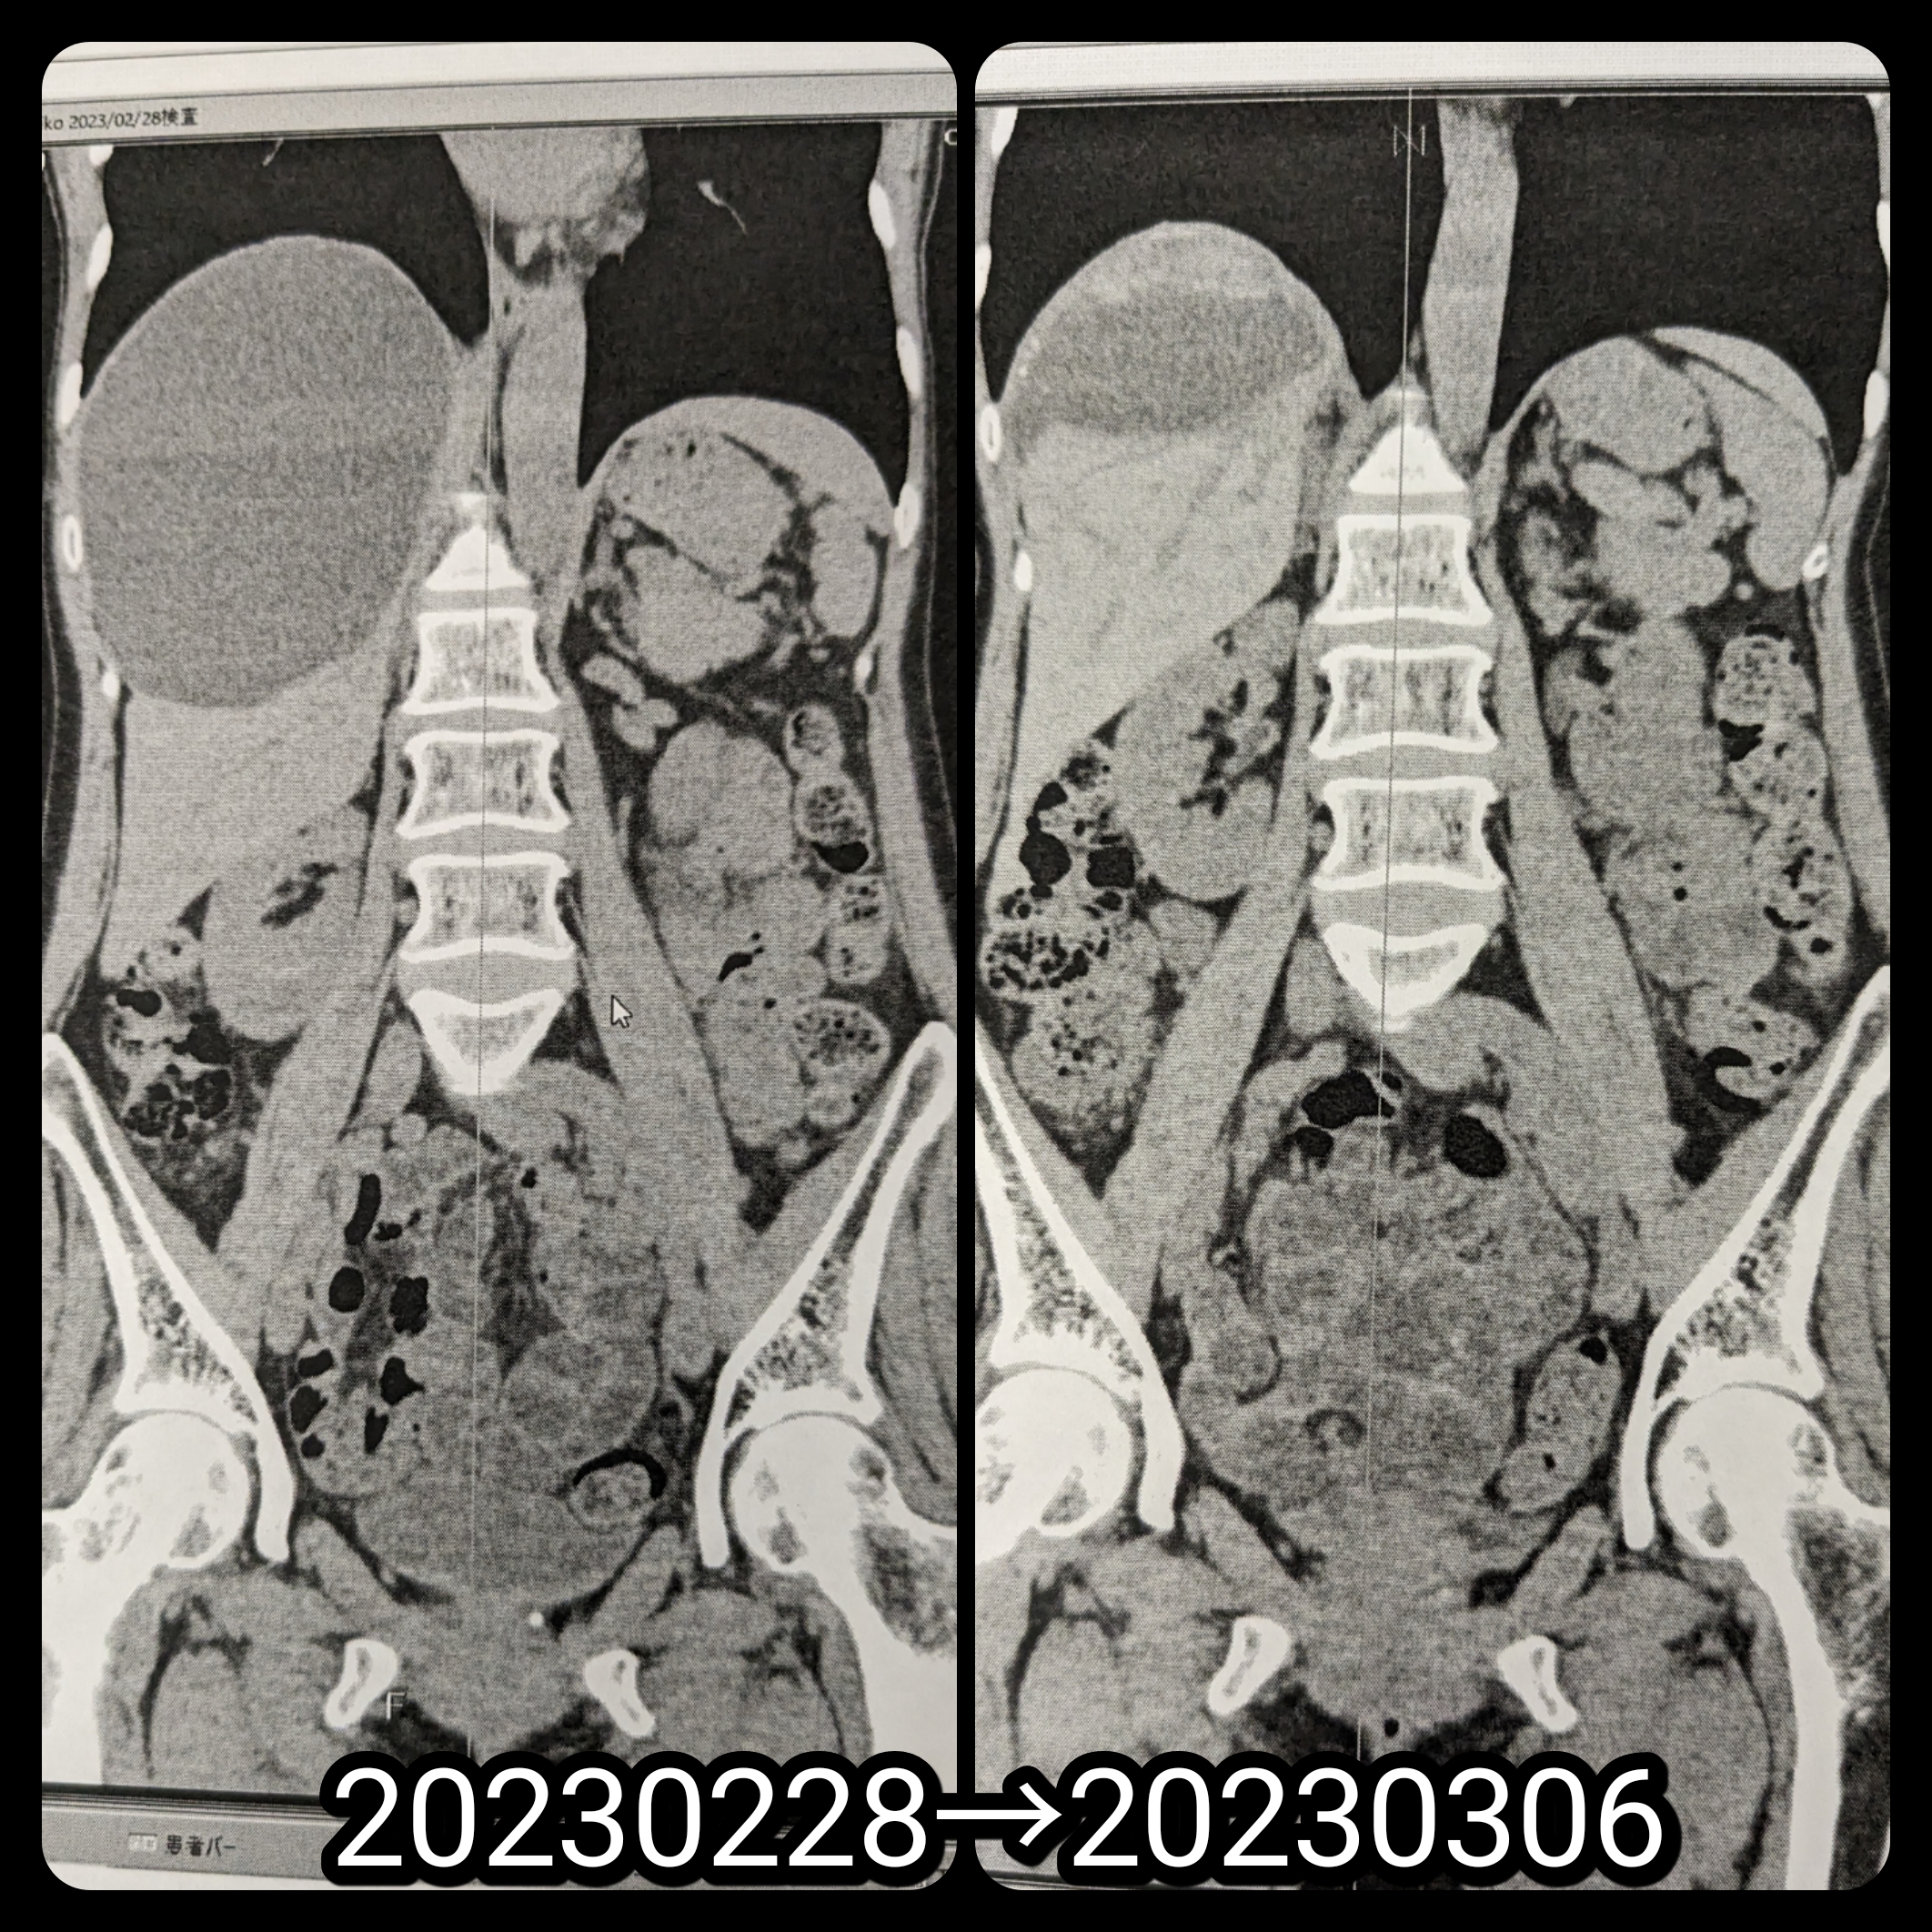

CT検査で

明日

退院決まった

14cm x 10cm

だったのが

9cmx6cm

現状は萎んだだけ

後は

経過観察

9cmx6cmでも

普通8cm以上は

大きいとされてるからねぇ

体積は1/4になってます

1ヶ月後

またCTで確認とのことです

巨大肝嚢胞Before→After